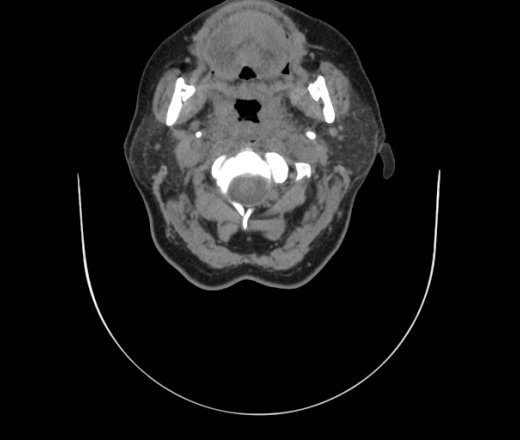

Женщина поступила в х/о спустя 4 дня после того как при употреблении карася подавилась костью.

Наличие газа в средостении на протяжении тел С2-С6 (медиастинальна эмфизема); рыбная кость на уровне тела С6.

При всем уважении, но говорить о медиастинальной эмфиземе, оценивая мягкие ткани шеи, как-то слишком резко. На мой взгляд, это ретрофарингеальное пространство.

Эвакуировали почти 100мл гноя. Но кость не смогли найти. Думаю что она даст дальнейшее ослоднение. Эндоскопически за черпалонадгортаной звязкой не смогли зайти в пищевод, все мягкие ткани отечные, просвет пищевода сдавлен. По всей видимости параэзофагеальная клетчака тоже задействована. Эмпиема, если ее можно так назвать, незнаю как правильно дошла до уровня яремной вырезки. Чем закончиться напишу. Ждем медиастинита.

Флегмона заглоточного пространства шеи, только операция, флегмоны вскрывают. Риск медиастинита.

Согласен с Вами; конечно, наличие газа в клетчатке ретрофарингеального пространства (затмение с опечаткой..). К сожалению, процесс "продвигается" к медиастиниту. Но почему никто, не отмечает наличие рыб. кости; или это для Всех очевидно?

Так вы уже отметили. Хотя ориентировал бы не скелетотопически, а на перстнечерпаловидный сустав.

Кость то мы сразу выявили, размеры где то 17*2мм, но ее так и не получается найти в этой каше